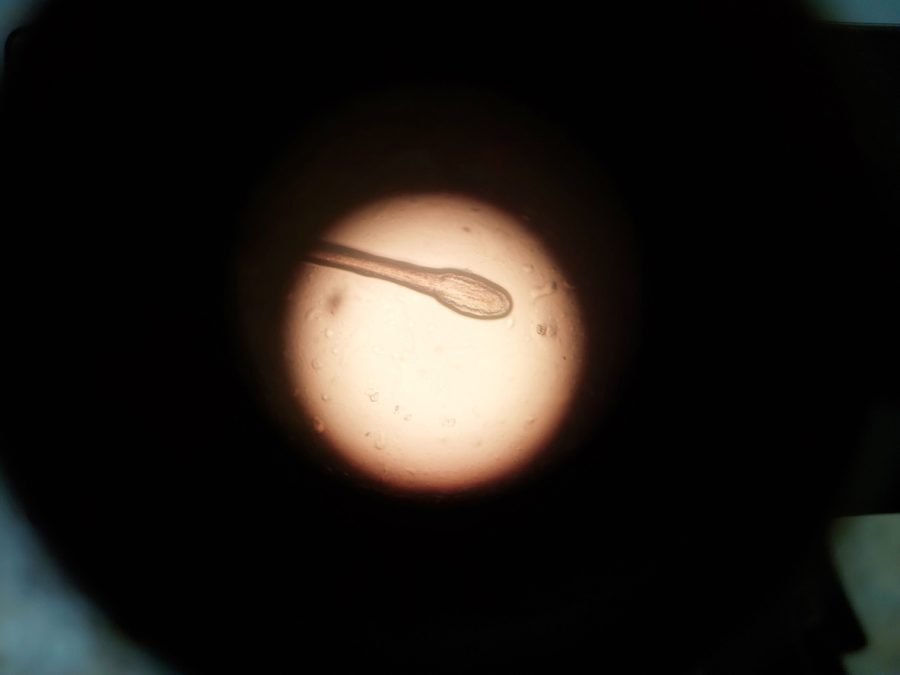

El hallazgo, publicado en la revista científica Frontiers in Immunology, reveló que varios pacientes compartían la misma variante genética (T328K del gen F12), todos concebidos mediante técnicas de reproducción asistida con un único donante.